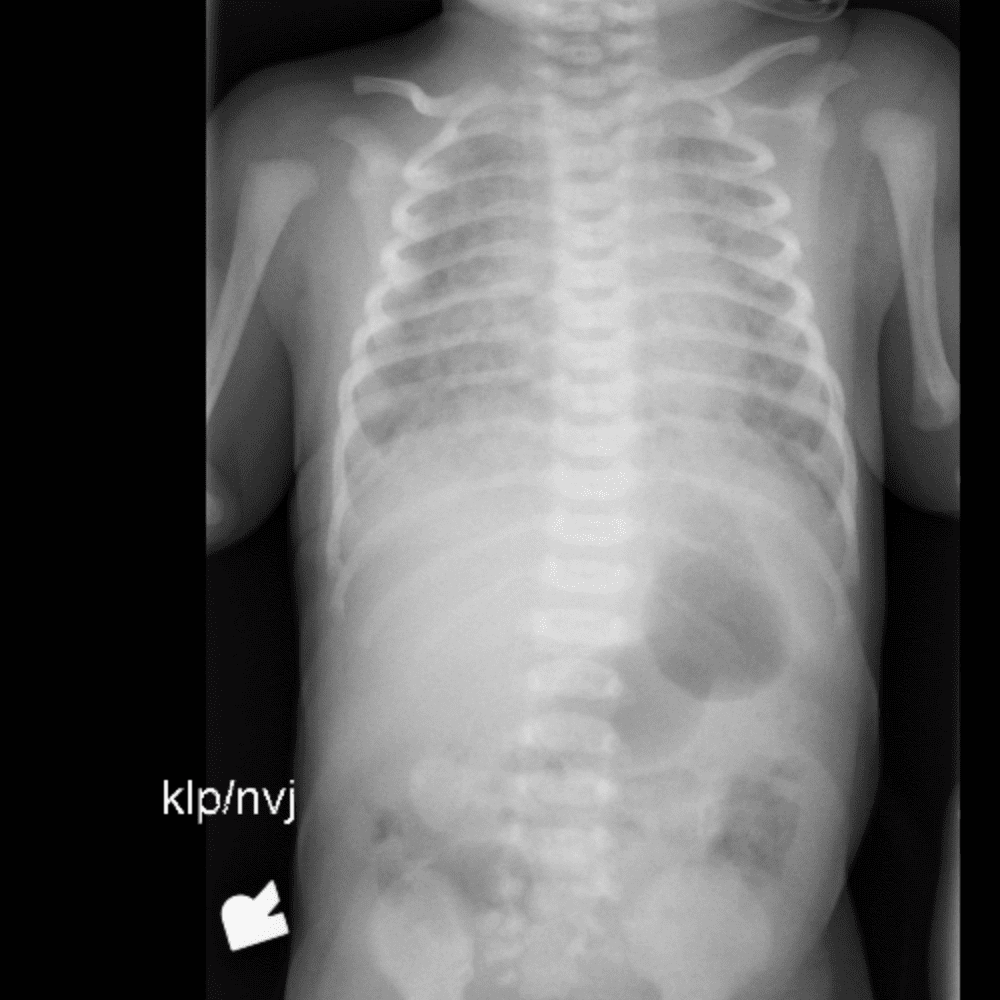

Peds Chest

Practice

Simulates call by including subtle or difficult cases and some normals.

50 cases